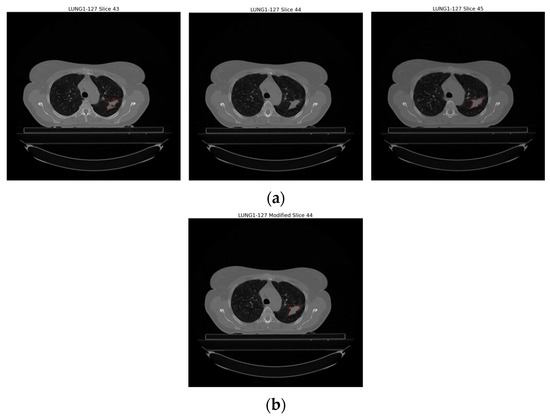

Improper images in the dataset given in the previous section were re-examined and solutions were developed against these incorrectly segmented images. As a result of the analysis, no solution was developed in Figure 5a because it was not possible to verify the error type by the clinician. Against the error type in Figure 5b, when there were sudden changes in the number of pixels covering the regions with each GTV-1 label, the relevant error was detected and the GTV in the slice where the error was found was made by interpolating between the slice before and the slice after where the errors were found. Figure 6 shows the update in the slice where the error was found. Against the error type in Figure 5c, it was determined whether the tumor was on the right or left, and only one region was focused on.

Figure 6. Illustration of the incorrectly segmented slice caused by interpolation in sequential segmentation in slices of an example patient (LUNG1-127). (a) Original version of Slice 43, Slice 44, Slice 45, (b) interpolation of Slice 44 based on Slice 43 and Slice 45.